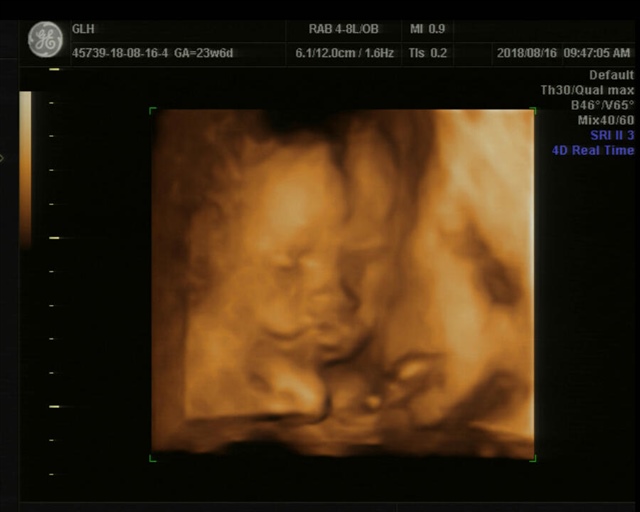

绿豆娃娃iHuf

第一个噘嘴照,太经典了